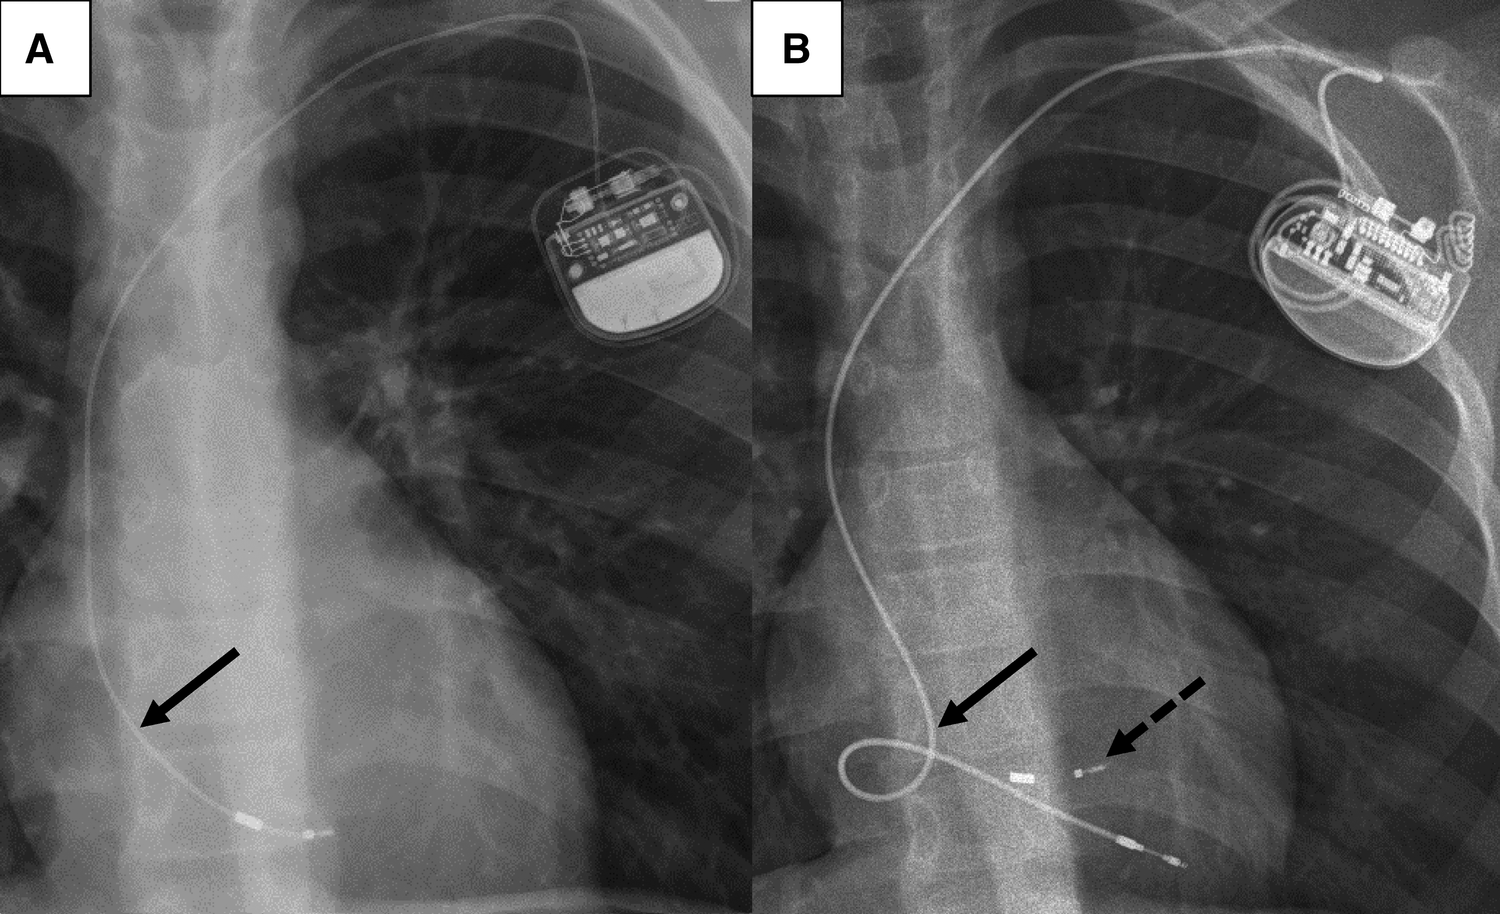

Figure 2

Chest radiographs of a 12-year-old boy before (A) and after (B) TLE. (A): depleted length reserve (arrow) of the right ventricular lead due to somatic growth. (B): lead length reserve for anticipated further somatic growth of the new lead implanted after TLE. The lead “reserve loop” is positioned in the right atrium (arrow). A fragment of the lead tip from the previously implanted 4472 model (Boston Scientific Fineline™ II) lead (dotted arrow) remained in the right ventricle. TLE, transvenous lead extraction.

Outcome characteristics are summarized in Table 4. Complete procedural success was achieved in 18 patients (64%) while clinical success was achieved in almost all patients (n = 27, 96%). Partial procedural success with retention of small lead fragments <4 cm were in particular observed with the Boston Scientific Fineline lead models 447x (4471, 4472, 4473, 4474) in our cohort. Frequently, these lead types fragmented just at the tip during extraction, and the lead tips could not be retrieved (Figure 2). The other lead type with only partial procedural success was a bipolar Osypka K5Y lead, which disintegrated at the tip during extraction and small fragments of the lead tip embolized to a hepatic vein. The additional use of femoral access for the extraction of lead fragments with snare catheters was significantly more often required with the 447x lead types compared to other lead types (10/21 vs. 1/20, Chi² p = 0.002).

The numbers of children and young adults with CIED therapy is increasing (26, 27). Children in particular have a limited durability of transvenous PM and ICD leads (3, 4, 7, 28). One reason for that is somatic growth related lead distortion and subsequent malfunction, which is frequently observed in children even though lead reserve loops, anticipating growth, are generally placed during CIED implantations (Figure 2) (7, 29). However, children with CIED therapy are dependent on functional leads for decades of life expectancy. Consequently, life time lead management strategies are mandatory and conservation of access vessel patency is paramount in particular. In fact, 8 of our patients (29%) had partial or complete thrombotic obstruction of the subclavian and/or innominate vein prior to TLE. While some authors have described uncomplicated short-term outcomes of abandonment of malfunctioning leads in young patients, long-term prospective studies are missing (25). Abandoning superfluent leads, in particular in children with smaller vessel dimensions, might impede later vascular access due to thrombotic venous occlusion (15, 30). Moreover, lead abandonment may result in interactions with other leads, cause regurgitation of the tricuspid valve/subpulmonary atrioventricular valve and increase the risk of infection (31). Also, abandoned leads may pose a contraindication for magnetic resonance imaging, although these concerns might require reconsideration in the light of more recent clinical data (32, 33).

Interestingly, in our study we demonstrate differences in extraction complexity and procedural success according to lead types. The 3830 model (Medtronic SelectSecure™) showed a decreased odd for complex TLE. After a median dwell time of 72 [IQR 49–95] months, 6/10 leads could be extracted by manual traction and all leads could be extracted with complete procedural success. The 3830 model is a polyurethane insulated lead that differs from other lead models by its low diameter (4.1F) and lumenless isodiametric design with a central cable, probably offering more tensile strength. Due to its small lead body dimensions it is frequently used in the pediatric population. A good extractability of the 3830 lead with a lower number of complex extractions and a higher procedural success rate has also previously been observed in cohorts of children and young adults as well as pediatric and adult CHD patients (16, 34). The 4471–4474 lead models (Boston Scientific Fineline™ II) are also small diameter leads (5–6F) often used in children with a coaxial design. In our cohort, we observed an increased incidence of partial procedural failure with the 447x lead family. In 9/21 leads, small fragments <4 cm length remained that could not be extracted. Typically, the lead fractured at the tip (Figure 2) Our findings are in line with a recent study that also reported a high rate of lead fracture during TLE in the Fineline™ family (35). Moreover, extraction of these lead model types might more frequently require complex extraction techniques (12). This was also observed in our cohort. A femoral approach with additional snaring of lead fragments was significantly more frequently required with Fineline™ leads.